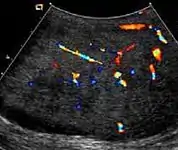

At ultrasound, the findings of acute epididymitis include an enlarged hypoechoic or hyperechoic (presumably secondary to hemorrhage) epididymis [Fig. 20a]. Other signs of inflammation such as increased vascularity, reactive hydrocele, pyocele and scrotal wall thickening may also be present. Testicular involvement is confirmed by the presence of testicular enlargement and an inhomogeneous echotexture. Hypervascularity on color Doppler images [Fig. 20b] is a well-established diagnostic criterion and may be the only imaging finding of epididymo-orchitis in some men.

- Doppler ultrasound of epididymitis, seen as a substantial increase in blood flow in the left epididymis (top image), while it is normal in the right (bottom image). The thickness of the epididymis (between yellow crosses) is only slightly increased (7 mm).

- Doppler ultrasound of the scrotum of the same case, in the axial plane, showing orchitis (as part of epididymo-orchitis) as hypoechogenic and slightly heterogenic left testicular tissue (right in image), with an increased blood flow. There is also swelling of peritesticular tissue.